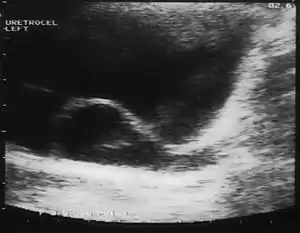

A ureterocele is a congenital abnormality found in the ureter. In this condition the distal ureter balloons at its opening into the bladder, forming a sac-like pouch. It is most often associated with a duplicated collection system, where two ureters drain their respective kidney instead of one. Simple ureterocele, where the condition involves only a single ureter, represents only twenty percent of cases.

Since the advent of the ultrasound, most ureteroceles are diagnosed prenatally. The pediatric and adult conditions are often found incidentally, i.e. through diagnostic imaging performed for unrelated reasons.

IVU-shows Adder head appearance or Cobra head appearance. Cystoscopy-shows translucent cyst which is thin walled surrounding ureteric orifice